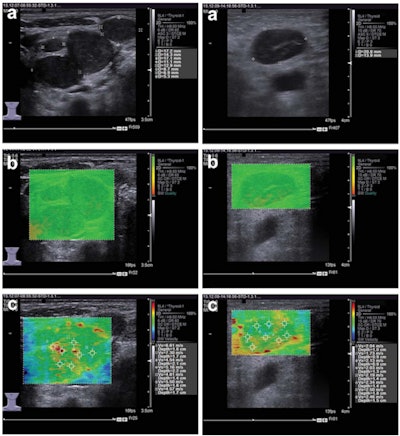

Left: Images of metastatic cervical lymph node. (A) Irregular low-echo nodules can be seen on conventional ultrasound, but the structure of the lymph node hilum is unclear. (B) Using "quality mode" on the VTIQ software, the lesion appears green with some yellow, showing good elasticity. (C) Using "velocity mode" on the VTIQ software, the shear-wave velocity values are shown for different points in the lesion. Right: Images of nonmetastatic lymph node. (A) An oval hypoechoic nodule can be seen on the conventional ultrasound, but the structure of the lymph node hilum is also unclear. (B) and (C), same descriptions as for previous image. All images courtesy of the Journal of Ultrasound in Medicine.False negatives